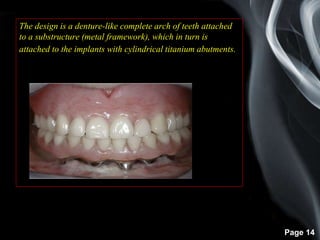

The design is a denture-like complete arch of teeth attached

to a substructure (metal framework), which in turn is

attached to the implants with cylindrical titanium abutments.

The prosthesis is fabricated without flange extensions and

does not rely on any soft tissue support. It is entirely

implant supported

Usually, the prosthesis includes bilateral distal cantilevers,

or first molars).